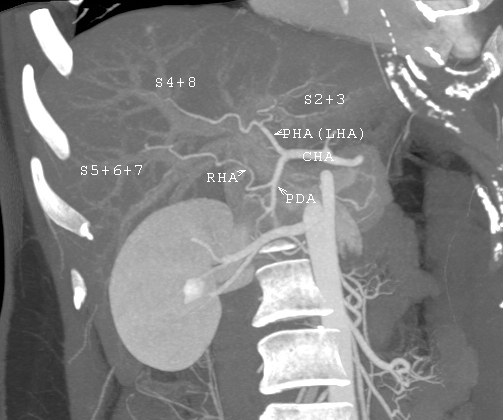

잠재적 기증자 평가를 위해 수행된 CT 스캔. 이 이미지는 특이한 간 동맥 변이를 보여준다.

생체 기증자는 가족 구성원, 부모, 형제자매, 자녀, 배우자 또는 자원봉사자가 될 수 있으며,[13][14] 건강 상태, 혈액형 일치 여부, 기증 동기, 연령, 체격 등의 기준을 충족해야 한다.[13][14] 생체 간 기증은 뇌사 기증에 비해 이식 대기 시간을 줄이고, 뇌사 장기 기증자를 기다리는 동안 발생할 수 있는 합병증과 사망 가능성을 낮추는 장점이 있다.